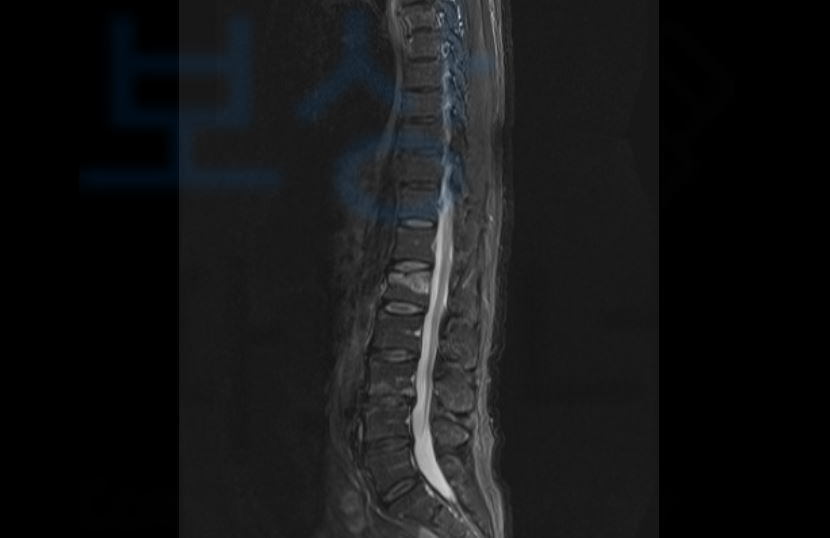

신@@님은 소방시설 공사를 위해 사다리를 이용하던 중 2미터의 높이에서 추락하는 사고를 당하셨습니다.

금번 사고로 병원에 내원하여 정밀검사를 받아보니…

요추1번압박골절과

경추부 염좌, 뇌진탕

좌측 견관절 염좌, 천골 골절

복부 좌상, 흉골 염좌 등의 진단을 받게 되었습니다.